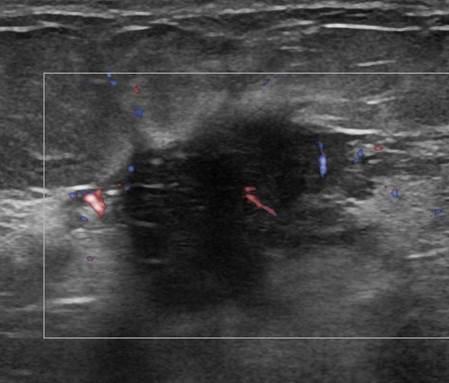

Ung thư vú

Ung thư vú - Ảnh 5

» Thông tin: Nữ giới – 58 tuổi.

» Lâm sàng: Khối tuyến vú.